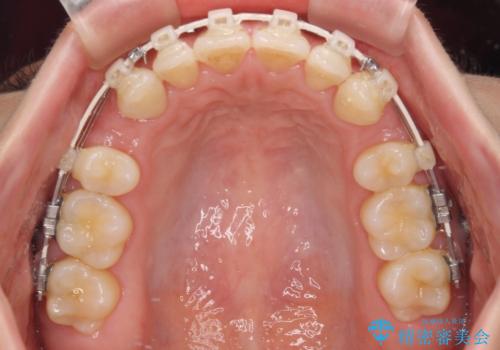

- 審美装置

- 上下前歯の隙間と口元の出っ張った感じを気にして来院された患者様です。

上下の隙間は舌突出癖によるもので、またその癖により前歯が前方に出ている状態でした。

口元の出っ張りを改善するため、上下左右第一小臼歯4本を抜去し、ワイヤー装置にて矯正治療を行うこととしました。

舌の突出癖を改善するためのトレーニングをしっかりと行っていただいたことで、比較的スムーズに治療を進めることができました。

口元の突出感もしっかりと改善することができました。